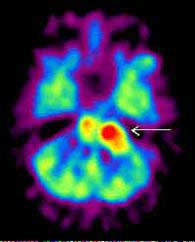

Рис. 2. Позитронная эмиссионная томография при злокачественной шванноме мозжечка. Очаг повышенного накопления 18F-ФДГ у пациента со злокачественной шванномой в левом полушарии мозжечка. Опухоль указана стрелкой (слева). В послеоперационном периоде в левом полушарии мозжечка определяется зона гипометаболизма глюкозы, что свидетельствует о радикальном удалении опухоли. Послеоперационная зона указана стрелкой (справа).